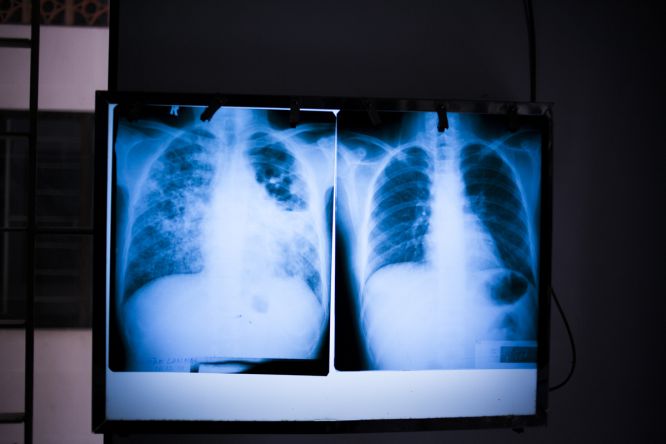

Lung x-ray of a healthy person (right) versus a patient with pulmonary TB (left). Cambodia rank second in the world in terms of TB prevalence of the disease, with 800 people per 100,000 having active TB. 60,000 people develop TB each year. The existing health system only identifies 25,000 to 30,000 of these cases, which is a huge gap in the detection of the disease.